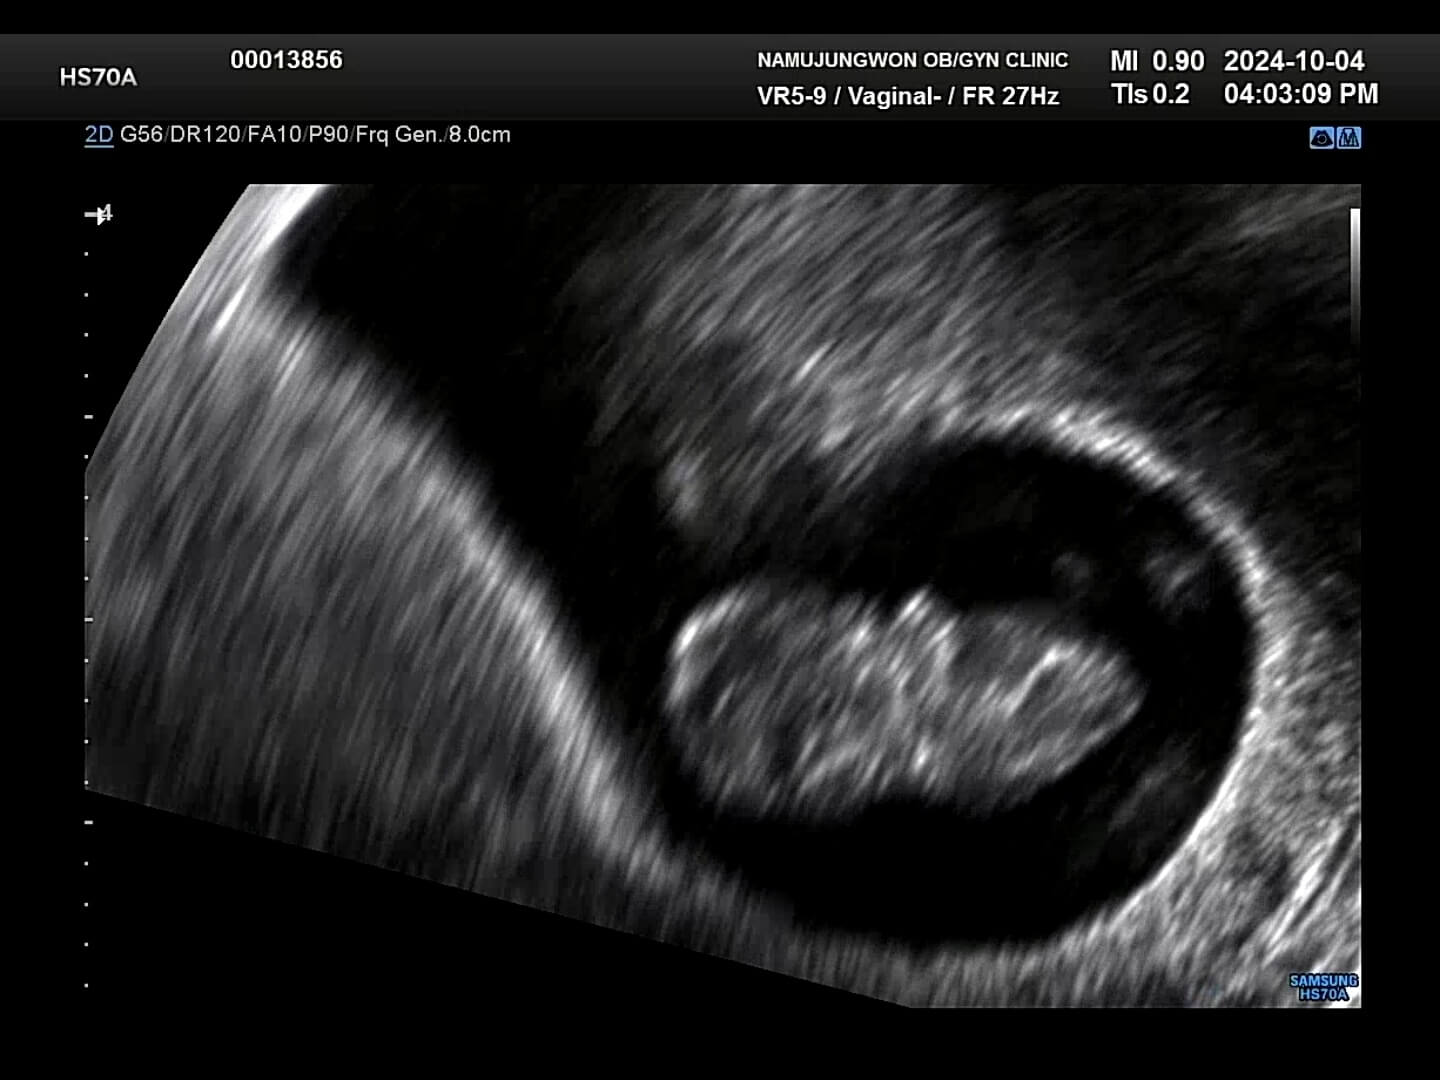

8주차-초음파사진 8주에서 9주 정도에는 초음파 사진을 보시면 아시겠지만, 손과 발이 나와서 마치 하리보 젤리의 젤리곰 같은 배아를 보실 수 있습니다. 거의 1~2주일만에 이렇게 큰 모습을 보니까 너무너무 귀여웠습니다. 2주만에 본 꾸미는 젤리곰이 되어서 꿈틀꿈틀 춤을 추고 있었고, 마치 짧고 귀여운 팔로 '엄마, 안녕!' 하는 기분이었어요.